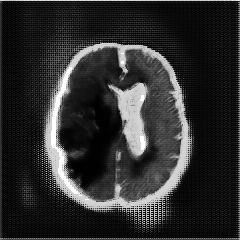

We introduce a neural network framework, utilizing adversarial learning to partition an image into two cuts, with one cut falling into a reference distribution provided by the user. This concept tackles the task of unsupervised anomaly segmentation, which has attracted increasing attention in recent years due to their broad applications in tasks with unlabelled data. This Adversarial-based Selective Cutting network (ASC-Net) bridges the two domains of cluster-based deep learning methods and adversarial-based anomaly/novelty detection algorithms. We evaluate this unsupervised learning model on BraTS brain tumor segmentation, LiTS liver lesion segmentation, and MS-SEG2015 segmentation tasks. Compared to existing methods like the AnoGAN family, our model demonstrates tremendous performance gains in unsupervised anomaly segmentation tasks. Although there is still room to further improve performance compared to supervised learning algorithms, the promising experimental results shed light on building an unsupervised learning algorithm using user-defined knowledge.